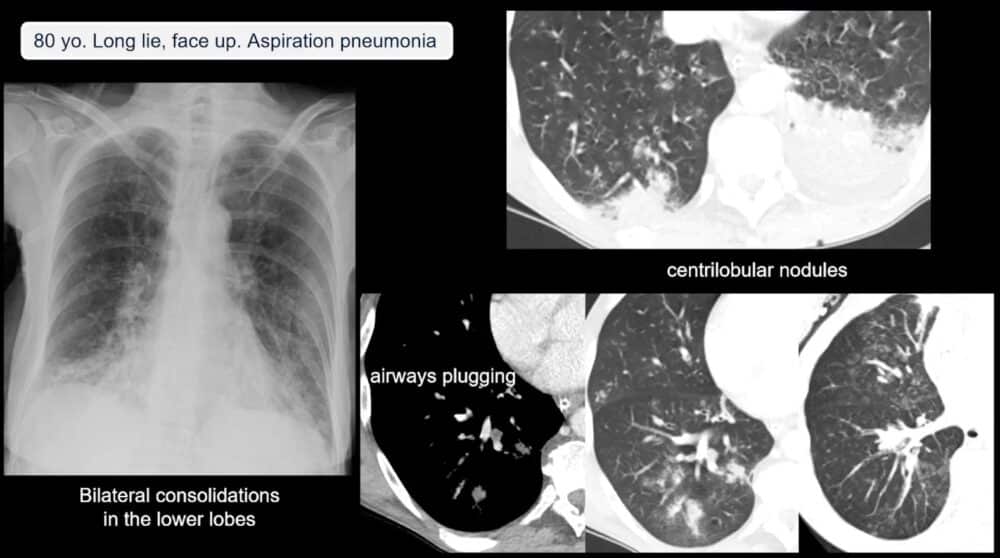

Moreover, falls in the elderly are often complicated by underlying medical conditions, such as strokes or infections, which may have caused the fall in the first place. In some cases, pneumonia or other respiratory conditions resulting from prolonged lying on cold floors can be identified through imaging. Dr. Blanco Barrio shared cases of aspiration pneumonia that were detected through CT scans, emphasizing how important it is to investigate these possibilities during imaging.